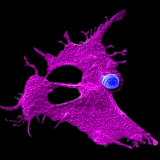

Microscopy image showing a stem cell-engineered CAR-NKT cell (blue) attacking a human solid tumor cell (magenta) against a black background

Cancer,

Science & Research

UCLA scientists develop one-product-fits-all immunotherapy for pancreatic cancer

UCLA researchers have developed a CAR-NKT cell therapy that has shown to be more effective than current immunotherapies at fighting tumors in several different mouse models of pancreatic cancer.